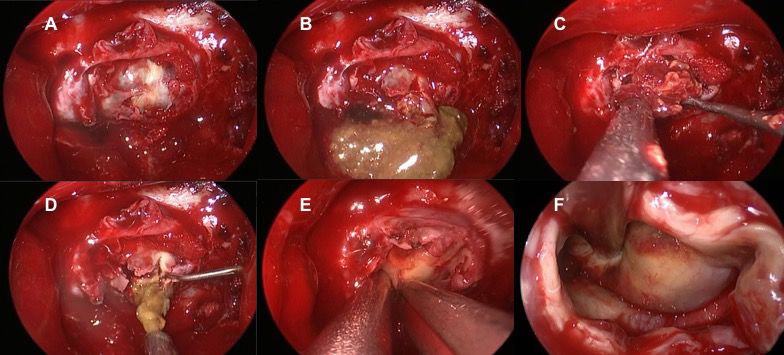

2017年12月20日在全麻下行内镜辅助下经鼻鞍区肿物切除术,术中磨除鞍底骨质后,可见肿瘤,肿瘤包膜较厚,剪开包膜后可见黄色胶冻样内容物,质地稀软易碎,刮匙完整刮除内容物,包膜与周围组织粘连紧密,部分剪除(图4)。术中送两次标本冰冻,结果分别是:嗜伊红色变性坏死组织;囊壁样纤维增生组织。术后标本送病理检查。

图4. A.咬除鞍底菲薄骨质,显露肿瘤;B.切开鞍底硬膜,黄变泥沙样内容物涌出;C.切除肿瘤,瘤体色红,稀软易碎;D.进一步刮除残余黄变内容物;E.剥除肿瘤残存包膜;F.肿瘤完整切除,残腔未见明显出血。